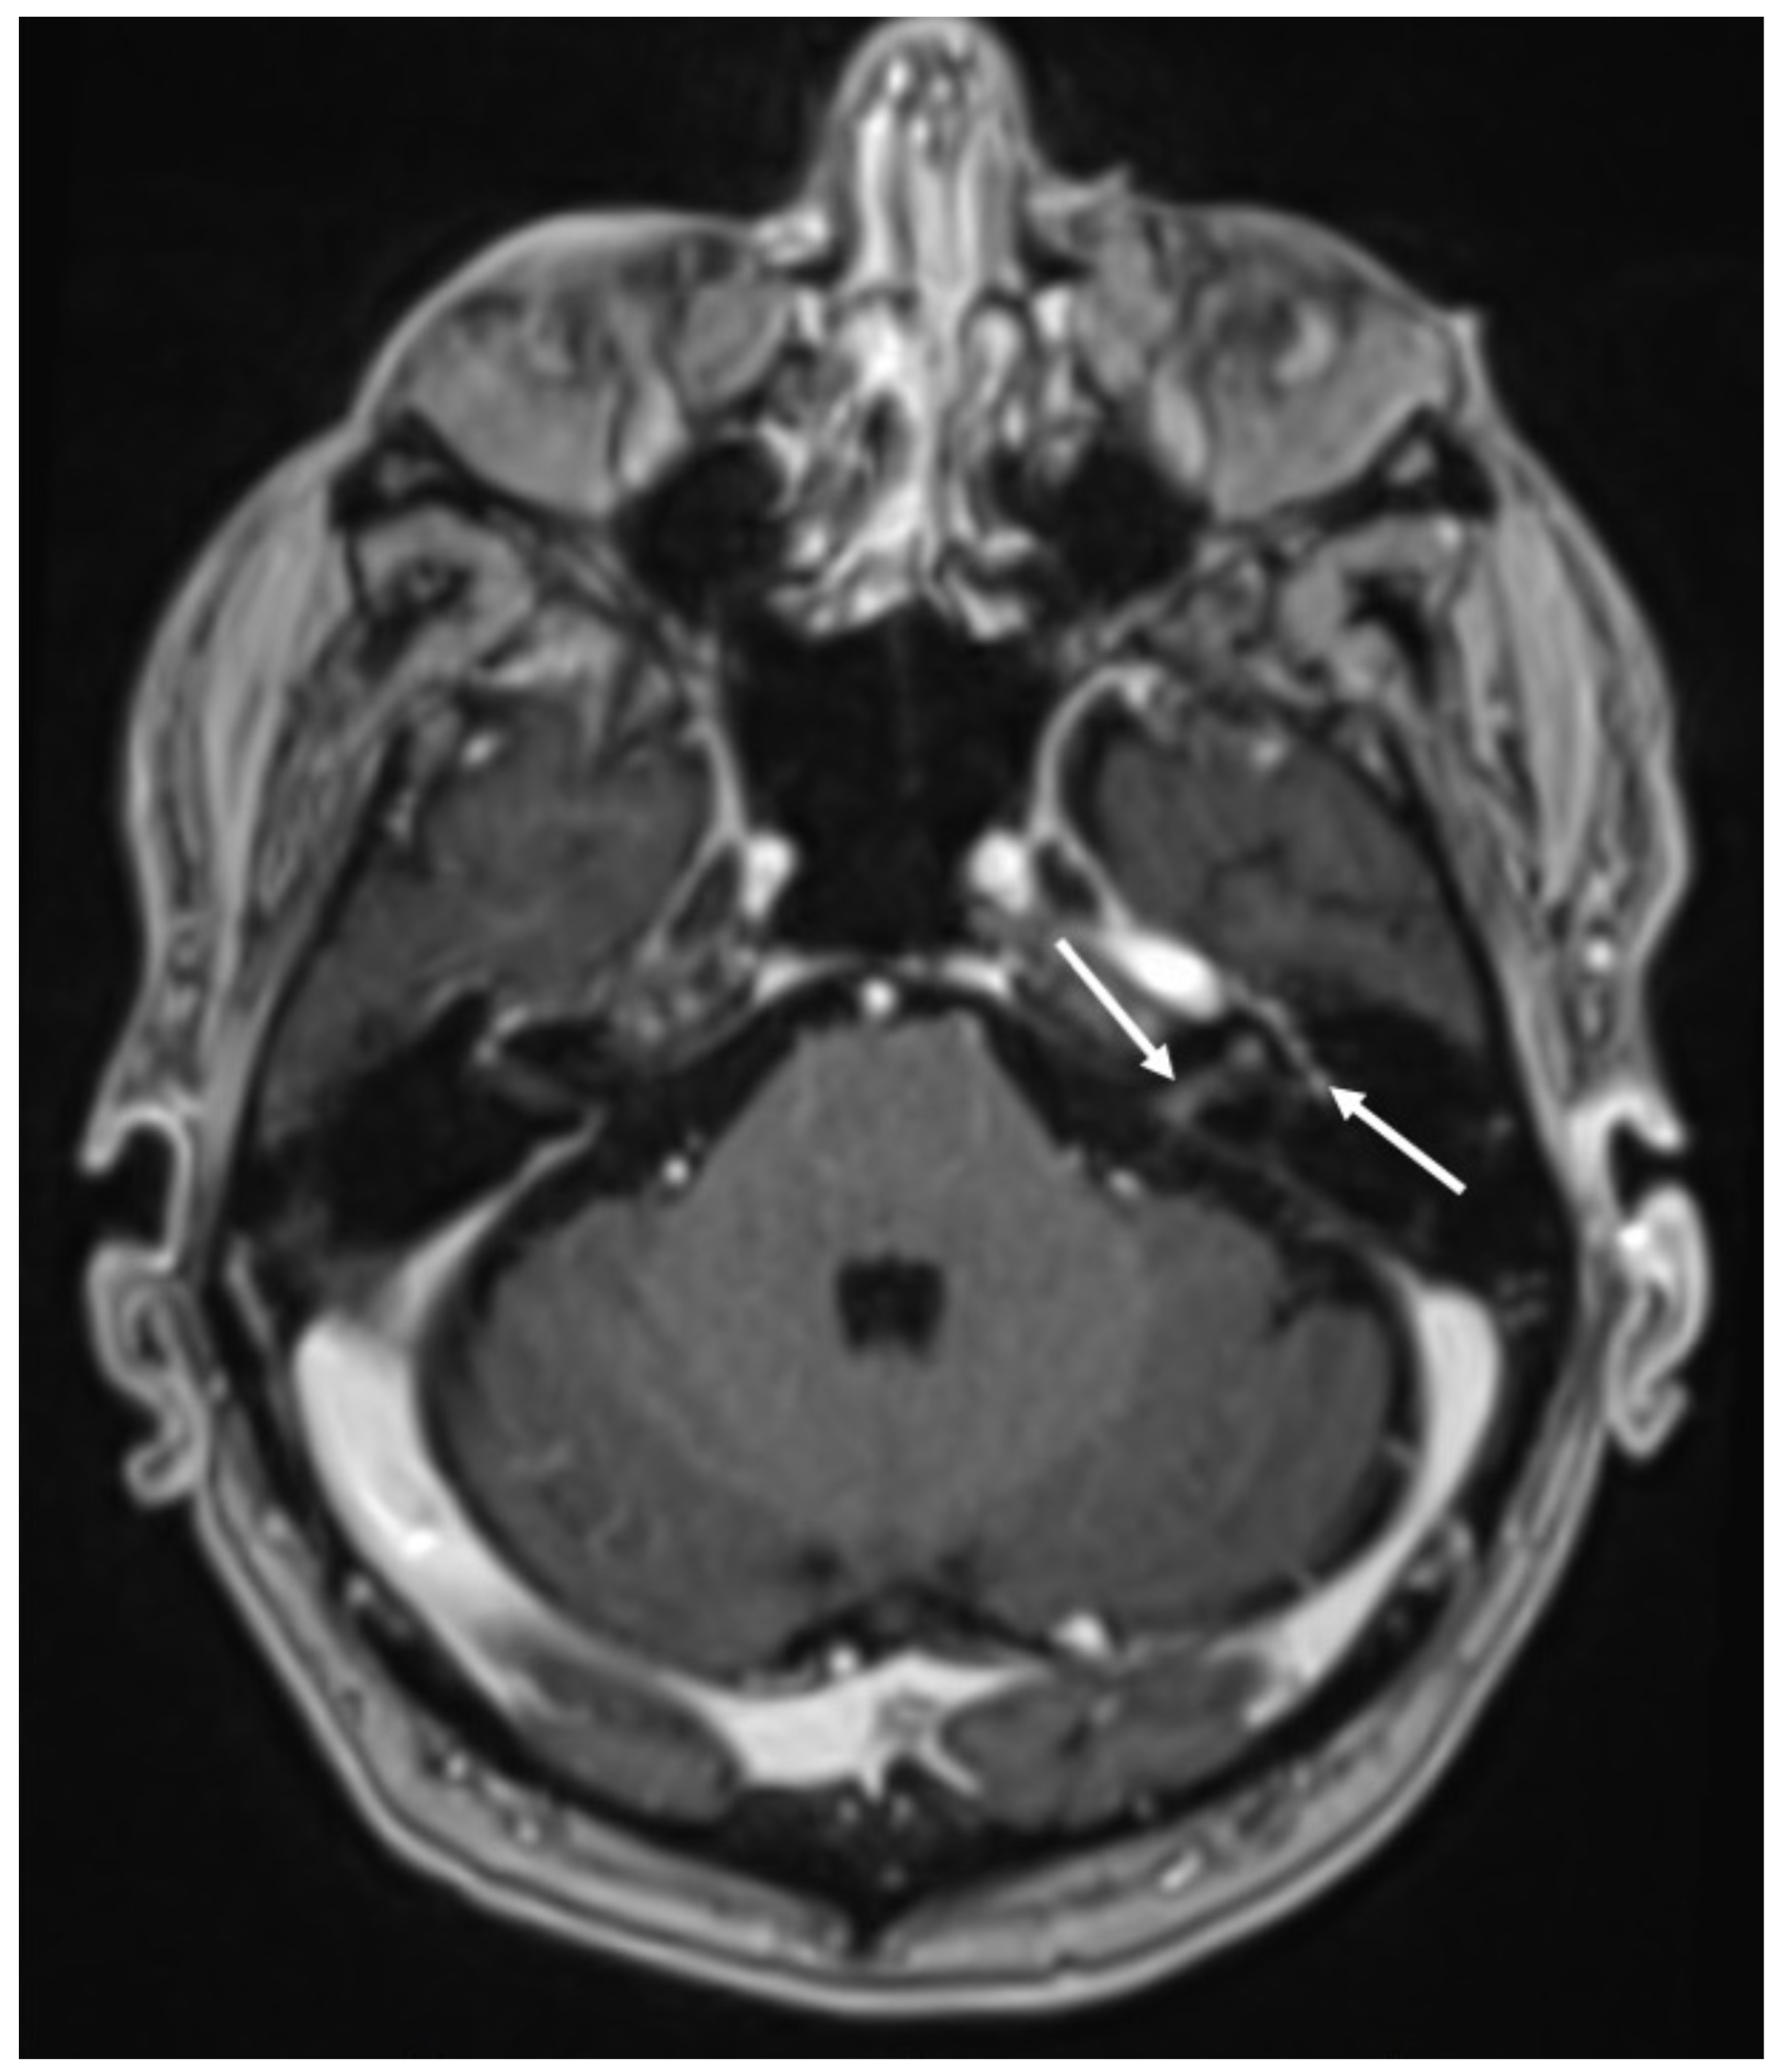

Figure 16.

Axial enhanced T1 shows enhancement of the left acoustic nerve and homolateral facial nerve (arrows) in a patient with Ramsay–Hunt syndrome.